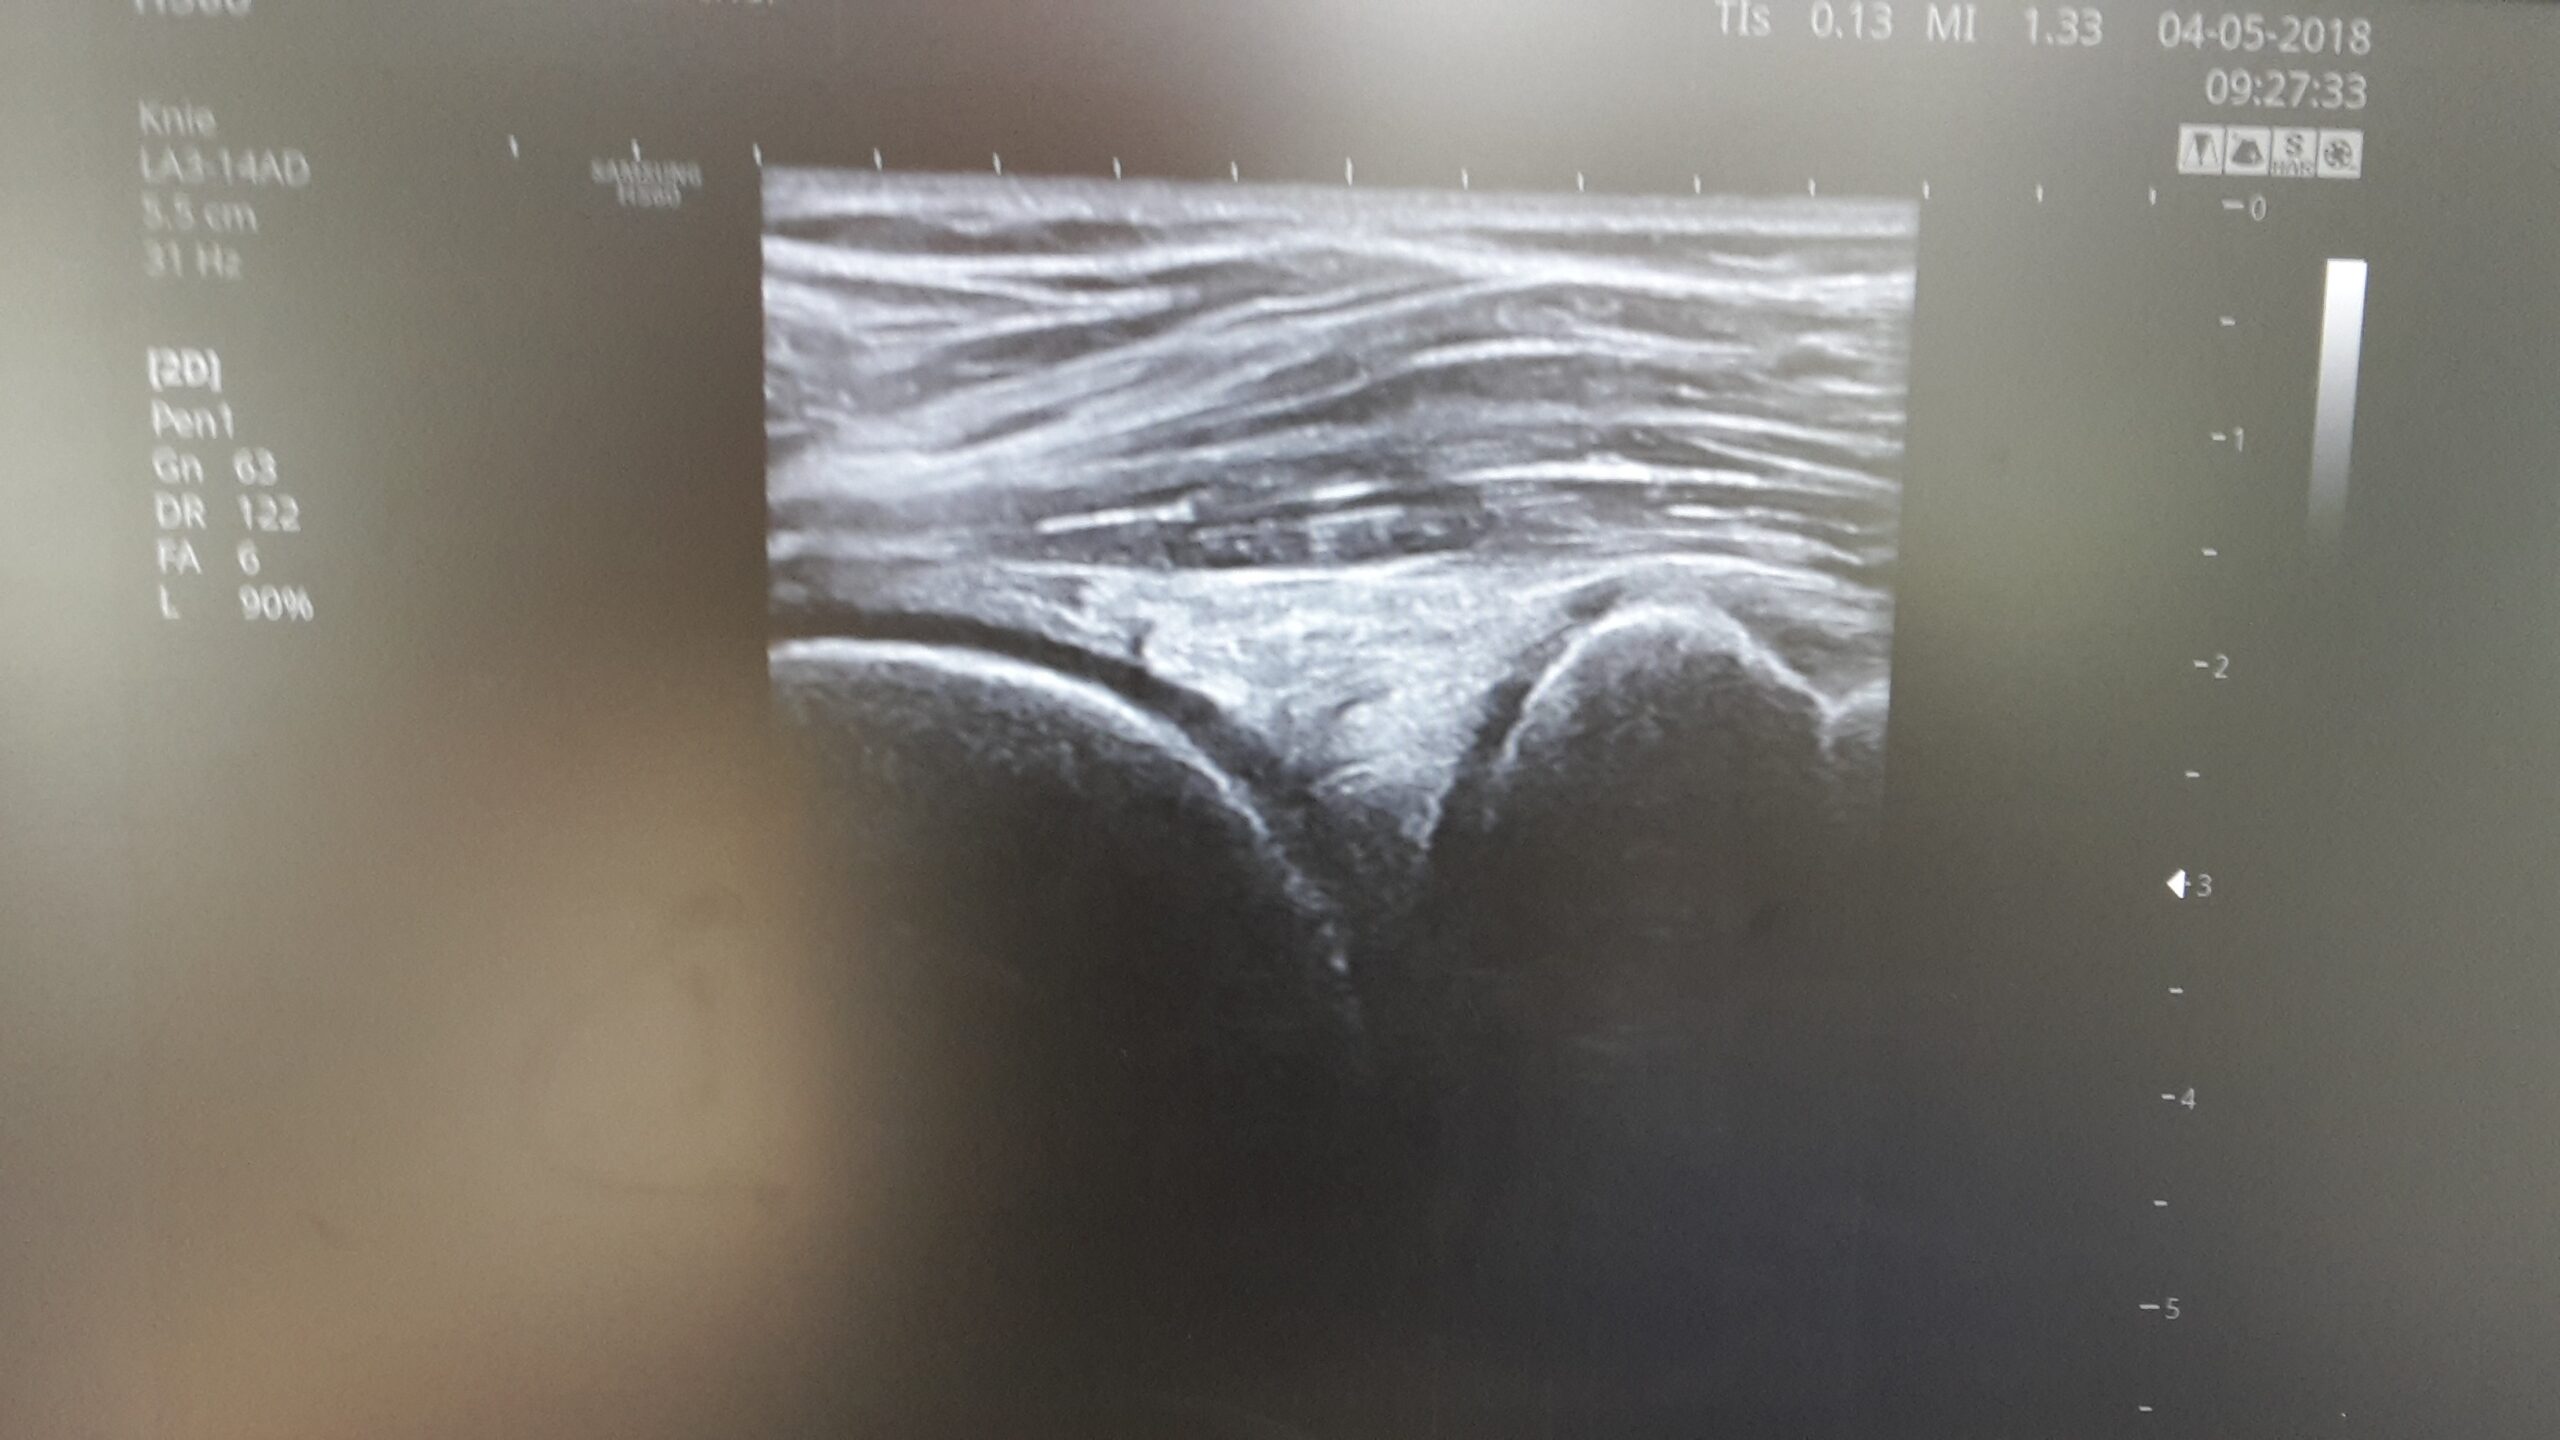

Herkömliche Ultraschallsysteme hatten bisher eine deutlich limitierte Auflösung- das heißt für uns dass wir gerade in der Feindiagnostik im Bereich von Muskelfasern, Faszien oder Nerven sowie Weichteiltumoren oder Meniskusstrukturen sehr oft an unsere Grenzen kamen und auf weiterführende und aufwändige Diagnostik angewiesen waren

Die neueste Ultraschallgeneration arbeitet mit hochfrequenten Sonden bis hinauf von knapp 40 mHz und ermöglicht uns eine bisher nie dagewesene Auflösungsqualität insbesondere im Nahfeldbereich zum Beispiel an kleinen Gelenken, Sehnen oder Nerven

Diese Systeme haben des weiteren eine Gewebesteifigkeitsmessung (Elastographie) sowie einen Farbdoppler an Bord – damit lasssen sich feinste Gefäßeinsprossungen ( pathologische Gefäße) in Sehnen oder entzündlich-rheumatische Prozesse nachweisen – mit der Elastographie erkennen wie feste Weichteilstrukturen zum Beispiel schmerzhafte Triggerknoten oder Faszienverklebungen und können damit weitere Therapiemaßnahmen effektiv überwachen und steuern.

Eine weiterer Vorteil der Sonographie ist die Möglichkeit einzelne oder komplexe Strukturen dynamisch-also in der Bewegung – zu untersuchen und hier Pathologien zu erkennen. Gerade bei der Untersuchung der Achillessehne oder des Meniskus sowie des Schultergelenkes spielt die Ultraschalluntersuchung diesen Vorteil sehr deutlich aus. Zudem ist die Methode relativ preisgünstig und ohne wesentliche Vorbereitung auch mobil einsetzbar.